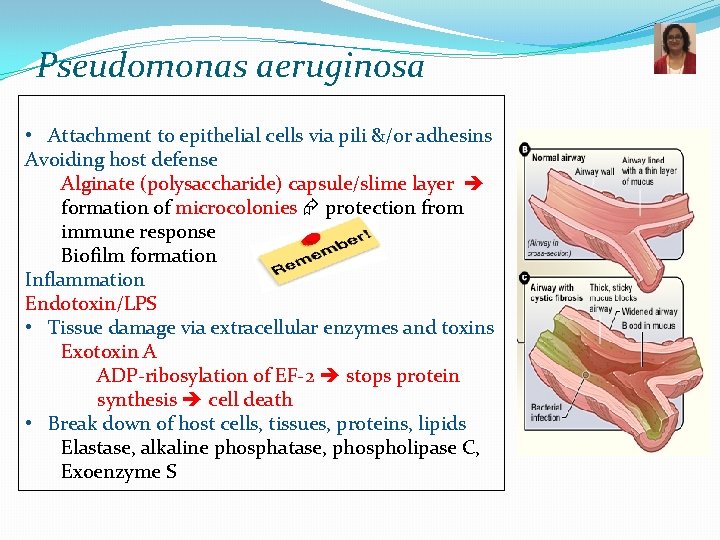

Pseudomonas aeruginosa • Attachment to epithelial cells via pili &/or adhesins Avoiding host defense Alginate (polysaccharide) capsule/slime layer formation of microcolonies protection from immune response Biofilm formation Inflammation Endotoxin/LPS • Tissue damage via extracellular enzymes and toxins Exotoxin A ADP-ribosylation of EF-2 stops protein synthesis cell death • Break down of host cells, tissues, proteins, lipids Elastase, alkaline phosphatase, phospholipase C, Exoenzyme S